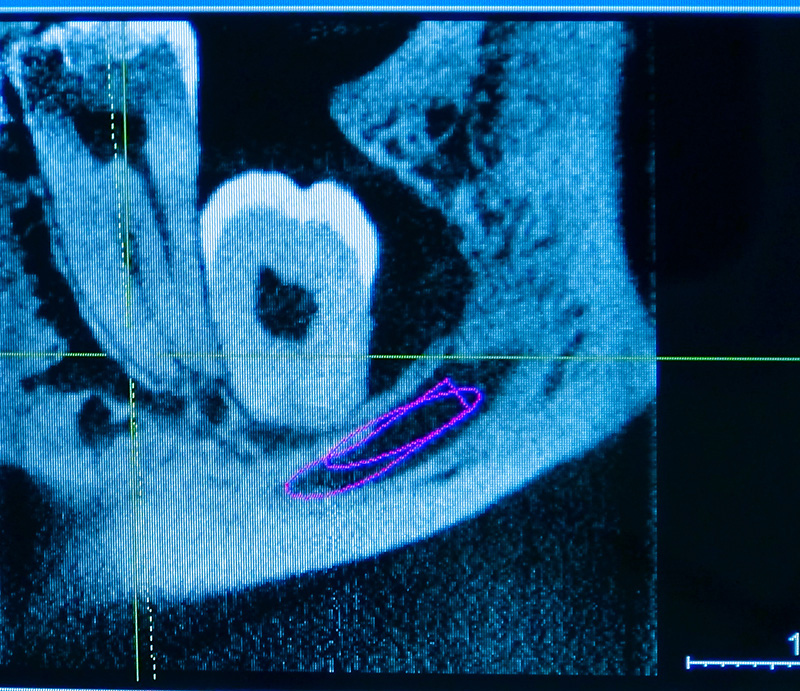

Allerdings bieten wir hier auch die Option einer kompletten digitalen 3D Planung an.